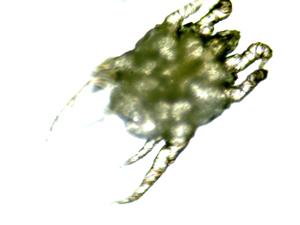

Ces mites sont des animaux microscopiques de la famille des acariens. Si elles colonisent le canal de l’oreille, elles se reproduisent en grand nombre et y prolifèrent aisément causant une réaction inflammatoire de légère à très sévère. L’intensité des signes dépend du nombre de parasites présents, de la résistance individuelle de l’animal et de la présence d’hypersensibilité ou d’allergie.

Le diagnostic définitif de la condition s’effectue en réalisant un frottis d’oreille (avec un coton-tige) et en observant le prélèvement au microscope. Bien souvent, on peut y voir une multitude de mites qui bougent, de larves et d’œufs de parasites. Parfois, le frottis ne démontre pas la présence du parasite parce qu’il y a trop de sécrétions dans l’échantillon. Si la suspicion clinique est fortement présente, un traitement pour l’otocariose s’avérera nécessaire même si le frottis est négatif.